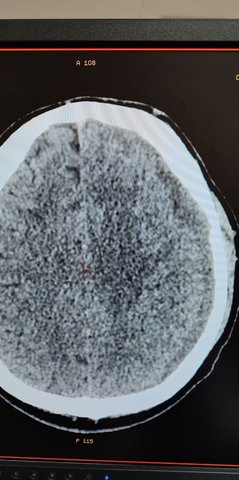

Метод был успешно применен у 39-летнего пациента, поступившего в нейрохирургическое отделение 18 декабря 2025 года, через 12 суток после получения тяжелой черепно-мозговой травмы. На СКТ в тот же день диагностированы очаги контузии обоих полушарий головного мозга и небольшого объема субдуральная гематома слева, вызвавшая значительное смещение структур головного мозга.

После детального обследования хирург Александр Майоров предложил применить новую тактику. Уже через четверо суток контрольная СКТ показала значительный регресс гематомы (не менее 20%) и уменьшение смещения мозга с 4 мм до 2 мм.